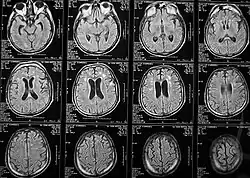

Магнитно-резонансная томография

Магни́тно-резона́нсная томогра́фия (МРТ) — способ получения томографических медицинских изображений для исследования внутренних органов и тканей с использованием явления ядерного магнитного резонанса. Способ основан на измерении электромагнитного отклика атомных ядер, находящихся в сильном постоянном магнитном поле, в ответ на возбуждение их определённым сочетанием электромагнитных волн. В МРТ такими ядрами являются ядра атомов водорода, присутствующие в огромном количестве в человеческом теле в составе воды и других веществ[1].

Томография позволяет визуализировать с высоким качеством головной, спинной мозг и другие внутренние органы. Современные технологии МРТ делают возможным неинвазивно (без вмешательства) исследовать работу органов — измерять скорость кровотока, тока спинномозговой жидкости, определять уровень диффузии в тканях, видеть активацию коры головного мозга при функционировании органов, за которые отвечает данный участок коры (функциональная магнитно-резонансная томография — фМРТ).